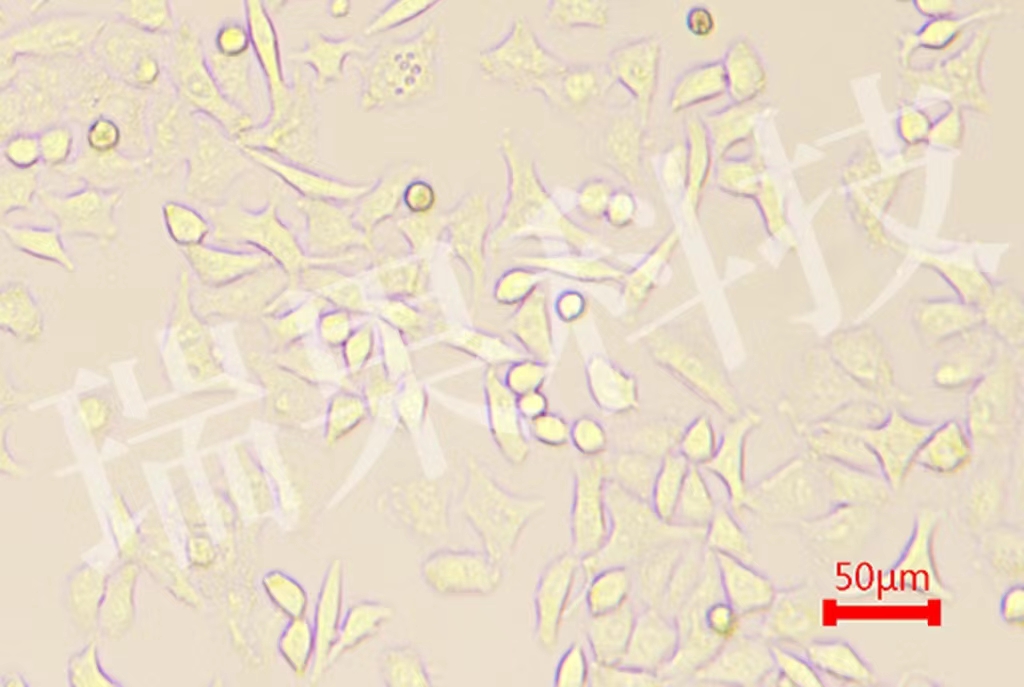

细胞周期是指细胞一个世代所经历的时间。从一次细胞分裂结束为一个周期。细胞周期反映了细胞增殖速度。单个细胞的周期测定可采用缩时摄影的方法,但它不能代表细胞群体的周期,故现多采用其他方法测群体周期,如BrdU掺入检测法。

BrdU(5-溴脱氧尿嘧啶核苷)加入培养基后,可作为细胞DNA复制的原料,经过两个细胞周期后,细胞中两条单链均含BrdU的DNA将占1/2,反映在染色体上应表现为一条单体浅染。经历了三个周期,赠染色体中约一半为两条单体均浅染,另一半为一深一浅。细胞如果仅经历一个周期,则两条单体均为深染。计分裂相中各期比例,就可以计算细胞周期的值。